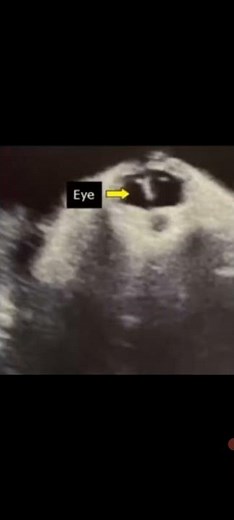

Sharks - Cyclops

Fish - Cyclops